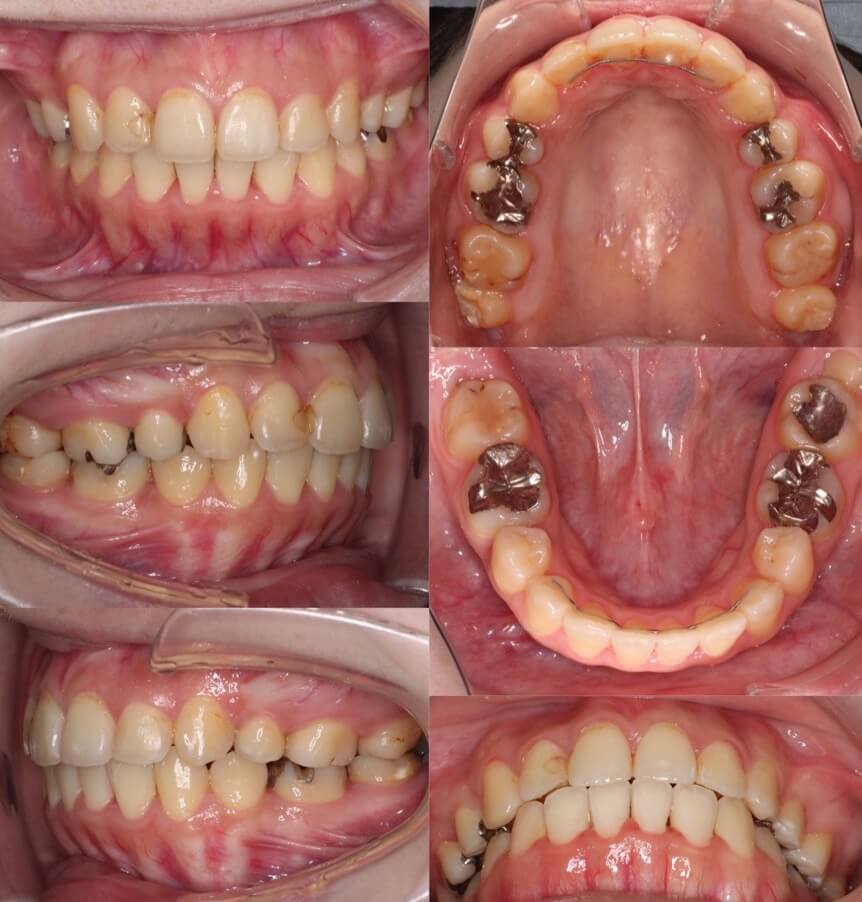

「前歯の角度が変化」

20代女性・ハーフリンガル装置・下あご後退型

前歯が前に傾斜している(倒れている)上下顎前突症例です。抜歯スペースに前歯を押し込むだけで、口元の突出が改善できる割と単純なケースになります。治療後は上下の前歯の角度も内向きに変わりました。

<症例概要>

主訴:前歯を引っ込めたい

年齢・性別:20代女性

住まい:千葉県佐倉市

症状:下顎後退・上下顎前歯唇側傾斜

治療方針:抜歯空隙の閉鎖(最大固定)

治療装置:ハーフリンガル矯正装置(上のみ裏側装置)

固定:歯科矯正用アンカースクリュー(口蓋側壁x2)

抜歯:上下第一小臼歯

治療期間:1年10か月

リテーナー:上下プレートタイプ+クリアタタイプ+フィックスタイプ

治療費用:1,4950,000(税込)

代表的副作用:痛み・治療後の後戻り・歯根吸収・歯髄壊死・歯肉退縮